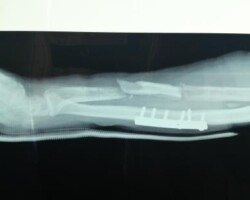

Αγγειούμενη περόνη

Άντρας 21 ετών υπέστη διπολικό κάταγμα της κερκίδας και κάταγμα της ωλένης, που αντιμετωπίστηκε σε περιφεριακό νοσοκομείο. 9 μήνες μετά διαπιστώθηκε ψευδάρθρωση της κερκίδας με οστικό απόλυμα 6,5 εκ. Αντιμετωπίστηκε με τη χρήση αγγειούμενης περόνης, η οποία γεφύρωσε το οστικό έλλειμμα της κερκίδας.